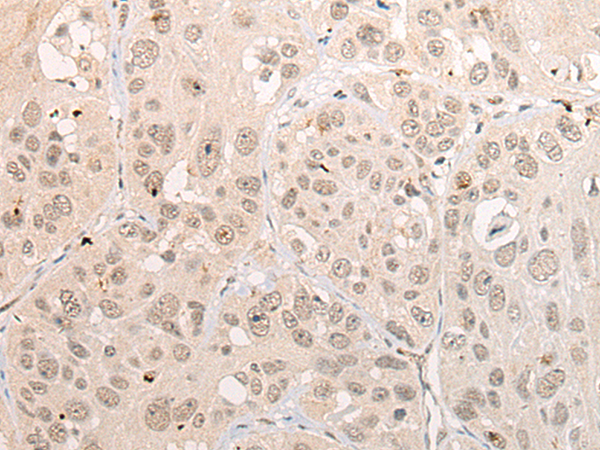

分类: 科研抗体货号: P09492别名: CGR11应用: IHC反应种属: Human